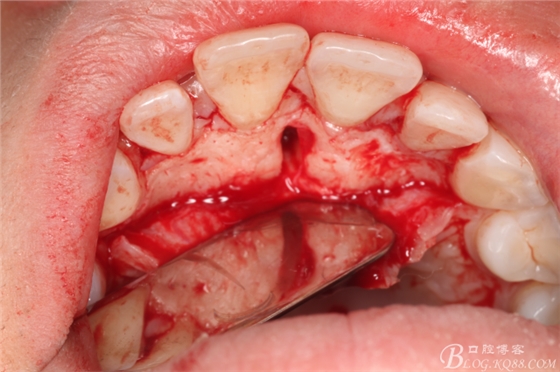

圖9.在切牙管旁邊去骨、暴露出21根尖區(qū)多生牙牙根

圖10.繼續(xù)去骨、發(fā)現(xiàn)多生牙部分位于鼻腭管內(nèi)

圖11、微創(chuàng)牙挺拔除多生牙

圖12.取出左邊上頜多生牙后,鼻腭管擴(kuò)大了,鼻腭神經(jīng)人那個(gè)腭側(cè)粘膜相連未斷。